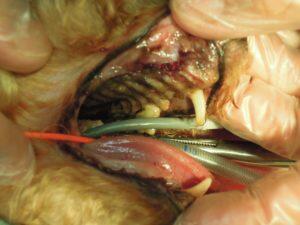

2.左側外観です。上顎犬歯の歯肉がかなり後退しています。

8.左側上顎の歯も全て抜歯し、